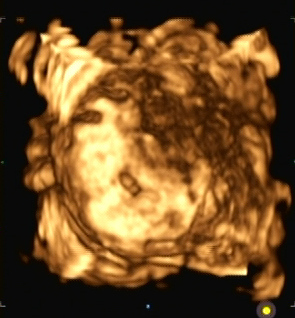

Ein zunächst durchgeführtes CTG war unauffällig. Im Rahmen der sonografischen Untersuchung zeigte sich der Fötus soweit beurteilbar zeitgerecht entwickelt. Dennoch konnte ein Anhydramnion festgestellt werden(Abb. 1, 2), weshalb auch kein fetales Gesicht darstellbar war (Abb. 3).